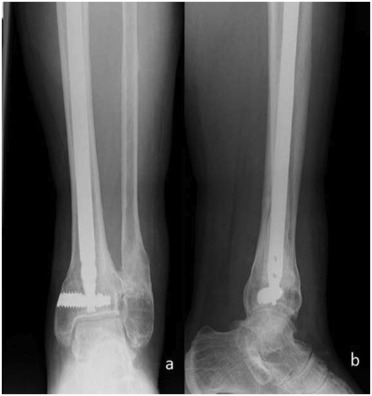

Patient 3

Fig. 4

Fig. 4.

Preoperative AP (a) and lateral (b) , and postoperative AP (c) and lateral (d) X-rays of Patient 3.

A 57-year-old male patient had an AO type A2-3 fracture of the tibia with no additional injury. He was operated at another clinic using an Ilizarov frame. He was followed up for 11 months with the Ilizarov frame, but no union was detected. He was then referred to our clinic. The Ilizarov frame was removed, and there was no obvious pin track infection (Fig. 4 a and b). The aforementioned protocol was observed to ensure the absence of infection, and the patient was operated using our new IMN system. The intramedullary Kirschner wire was removed, and the ununited segment at the fibula was removed. The ununited segment of tibia was opened medially, and fibrous tissue was removed using curettes. An autograft harvested from the healthy bony ends of the fibular nonunion site was used. A 42 × 8 mm DSBLS was inserted 2 mm above the ankle joint. Our new IMN (360 × 12 mm) was inserted proximally through the distal fragment. After completing interlocking, alignment and correction were reassessed using tibiocalcaneal angle under fluoroscopy. Correction was assessed with postoperative AP-lateral X-rays (Fig. 4 c and d).